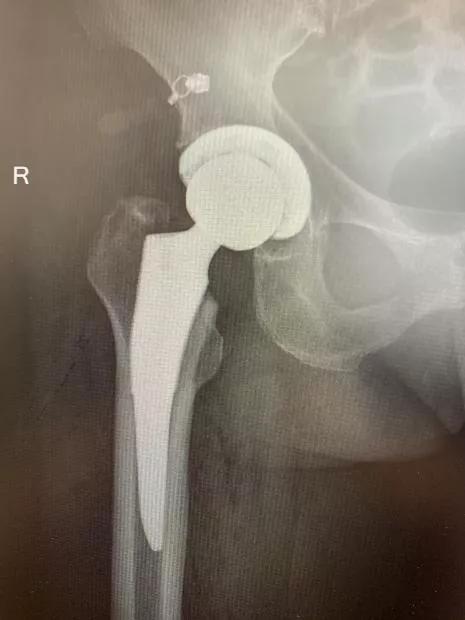

▲术后 X 光片显示:右髋假体、右膝假体位置角度放置与术前规划一致。